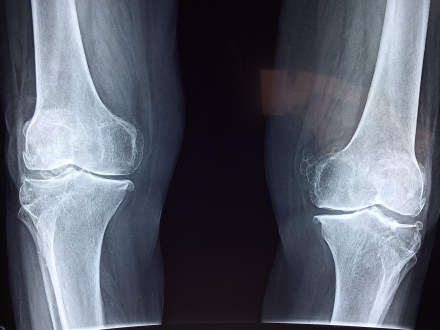

Scientifically speaking, bone formation continues until the age of 20 years, reaching a peak at 30. After 30, the breakdown exceeds formation and bones slowly decrease in density. If the body is unable to maintain adequate bone formation, bones continue to lose density and may become increasingly fragile, eventually resulting in osteoporosis.

Most people have deficiencies in their 20s, 30s or 40s leading to long-term bone health issues after 60s. The real problem starts after the age of 60 years, when you experience broken bones that require treatment. At that stage, many people ask, “Why do my bones get fractured so easily?” According to Dr Debashish Chanda, lead consultant, department of orthopedics, C K Birla Hospital, Gurugram, the problem starts in the initial stages of one’s life when vitamin D could have answered all such queries. “Even regular exercise can keep the bones healthy. Many women have low bone density at the age of 50 as they hit menopause, which can also result in osteoporosis. Beyond 50, it is important to check bone density. Both men and women must get their bone density checked after 2-3 years at the age of 60. It is the right age to prevent fractures,” says Dr Chanda.

Dr Chanda further advises to go for core bone density check up instead of whole bone density. The reason is that the skull and pelvis bone never get soft and last till we die, so the whole body density test can give false results. “It is important to screen the areas which have a high tendency of fractures like legs, hands and neck,” he adds.

Food supplements like nuts, turmeric, sesame seeds, and desi ghee are all natural ingredients to increase bone density. “Let’s compare this with a normal wood vis-a-vis a termite-eaten wood. A termite eaten wood is osteoporosis whereas osteopenia is somewhere between normal wood and termite eaten wood. Osteopenia is a clinical term to describe a decrease in bone mineral density below normal values, yet not low enough to meet the diagnostic criteria to be considered osteoporotic. Some parts are osteoporotic and some are strong. For example, some have weak hip bones and spine bones or vice versa. The diagnosis of osteopenia is important at this stage, ” adds Chanda.